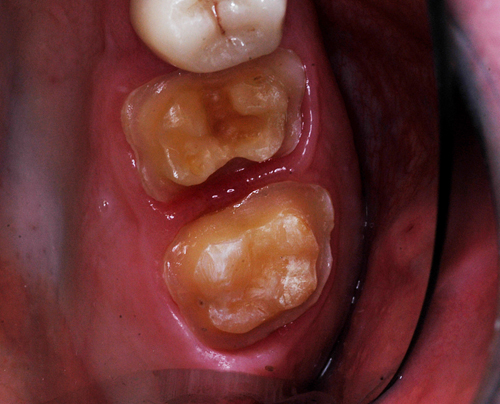

REHABILITACION ORAL MEDIANTE CORONAS DE PORCELANA DE ALTA DENSIDAD Protocolo D.A.T.O. CASO CLINICO: Paciente 24 años, bruxómano, atresia maxilar, referido por ortodoncista para realizar rehabilitación oclusal . Se observa a la inspección la presencia de una hipoplasia adamantina en todos los dientes anteriores, carencia de Guía Anterior , evidentes signos de Facetas Parafuncionales de Desgaste en los posteriores, y una marcada convergencia de los ejes dentarios ápico oclusal, tanto en el maxilar superior como en el inferior, siendo el superior el mas difícil de resolver dado que la inclinación de la Curva de Wilson es inversa a lo que presenta el enfermo. Radiograficamente sin patologías presentes. No presenta movilidades dentarias ni síntomas articulares en las ATM. Debido a la excesiva contractura de su musculatura, se realiza la relajación obviando el uso corriente de las Laminillas de Long, reemplazando el método por un Jig de Lucia el que se deja en boca desde la noche anterior a la cita, advirtiendo al paciente que no debe quitarlo en ningún momento , ya que de hacerlo se repetirían los engramas musculares anómalos que el enfermo presenta. En esas condiciones se toman registros intermaxilares mediante silicona de registros, y se registra el maxilar superior respecto del plano de Frankfort mediante arco facial estático. Se llevan a cabo los encerados correspondientes y se construye en base a ellos el primer juego de provisionales, los que no son cementados debido al perfecto anclaje que presenta. Transcurridos seis meses del uso de provisionales , durante los cuales se ha observado la Oclusión en Relación Céntrica (ORC) inalterable, la ausencia de desgastes patológicos (en las provisorias) y la ausencia de síntomas articulares y musculares, deducimos que el paciente se mantiene en una orto función adecuada, por lo cual comenzamos su rehabilitación definitiva construyendo su Guía Anterior ( determinante primario de la oclusión) en porcelana sobre porcelana de alta densidad.. Observamos los espacios correspondientes en los sectores posteriores y las Disclusiones de los mismos. Los tallados ha sido realizados mediante el concepto de Tallados Gnatológicos, recreados por el Prof. Alvarez Cantoni bajo la denominación de “Preparaciones Racionales”( PREPARACIONES RACIONALES EN PRÓTESIS PARCIAL FIJA. Ed. Hacheace) probando finalmente el trabajo luego de varios días de cementado provisional, y observando la adaptación periférica del borde cavo superficial , su aspecto estético y el importante factor disclusivo : CURVA DE WILSON. y verificando la eficacia lograda mediante una Oclusión Mutuamente Compartida, en la observación de una Disclusión derecha en el Lado de Trabajo y no Trabajo de una disclusión izquierda como así también en la disclusión propulsiva Utilizamos papel de articular de ocho(8) micras para verificar la eficacia de las disclusiones. y de los puntos interoclusales de contacto ANTES DESPUES

Luego de un par de entrevistas, se le informa acerca de la hipofunción masticatoria evidente, producto de la destrucción no solo de las piezas anteriores, sino también de la paulatina generación de Facetas Parafuncionales de Desgaste que determinan una eficacia masticatoria deficiente.

Facetas estas donde puede observarse el típico fenómeno de “DESGASTE EN OLLA”, constituido por el facetamiento doblemente profundo de las Cúspides Estampadoras respecto de las Cúspides de Corte.